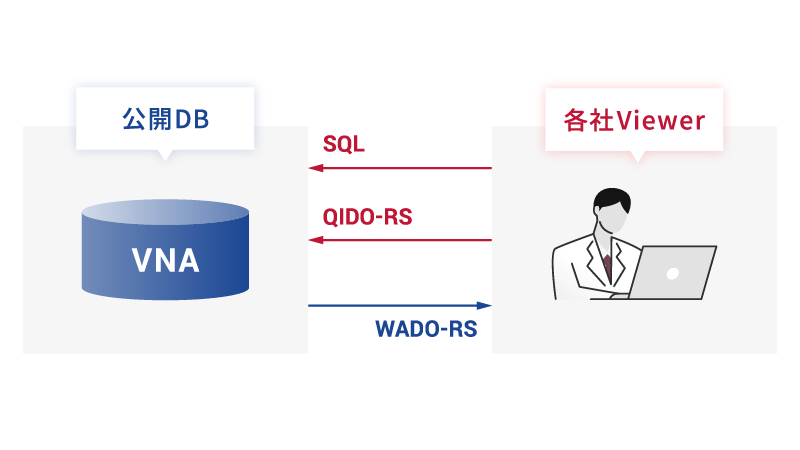

高速アクセス・高速表示

高速アクセス・高速表示

フォーマットやプロトコルの互換性を最大限に確保し、システムの連携を容易にします。

これにより、シームレスなデータの統合・管理が可能となり、時間の節約やスムーズな情報共有を実現。また、端末制限を受けない画像閲覧環境を実現します。

さらにDICOM web(WADO-RS/QIDO-RS)+OCDB(Open Connect Database)に加え、SQLで柔軟に情報を取得することによって画像の高速表示を実現します。